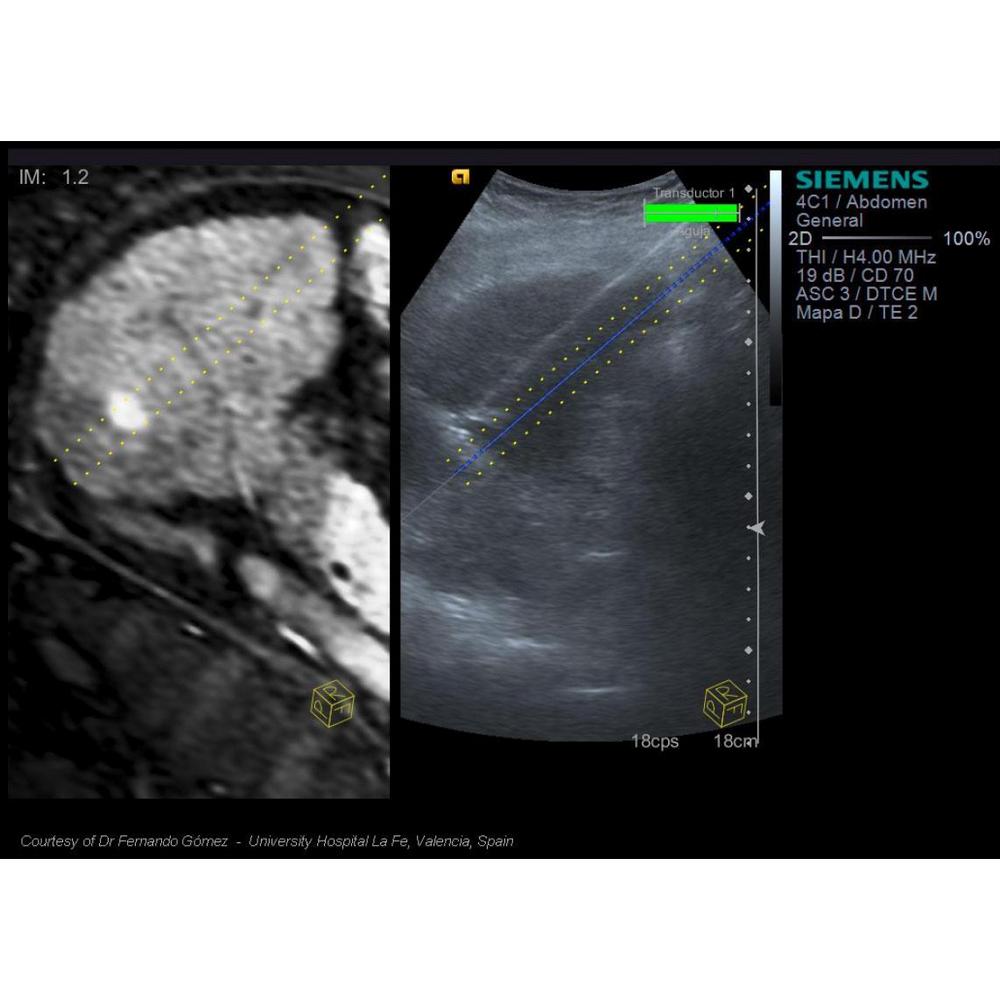

- 3D-изображения КТ и МРТ в сочетании с ультразвуковым изображением в режиме реального времени.

- Важнейшая информация о патологическом процессе, необходимая для проведения интервенционных процедур, и комплексный анализ всего массива данных.

• Возможность совмещения текущего изображения УЗИ с результатами КТ и МРТ в режиме онлайн.

• eSieGuide – улучшенная биопсийная игла для инвазивных исследований.